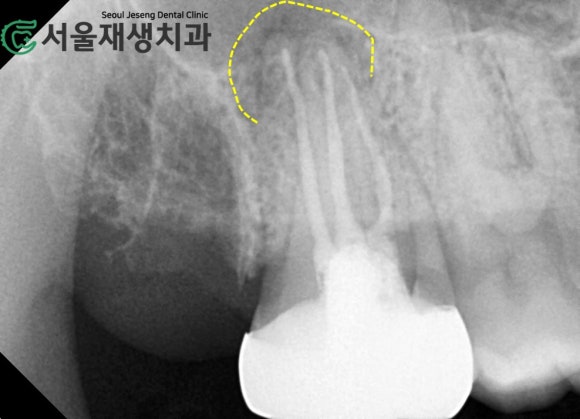

치근단 엑스레이를 촬영했습니다.

파노라마가 단체사진이라면

치근단 엑스레이는 증명사진입니다.

단체사진을 확대한다고 얼굴의 주근깨나 점이 다 보이지 않지요?

치아도 필요에 따라 치근단엑스레이 촬영을 시행하면, 보다 자세하고 풍부한 정보를 얻을 수 있습니다.

다행히 염증의 크기는 발치를 고려할 정도로 크지 않습니다.

적절한 재신경치료가 시행된다면

염증이 사라지는 것은 물론이고, 치아에게 제2의 인생(?)을 선물하는 기회가 될 것 같습니다^^